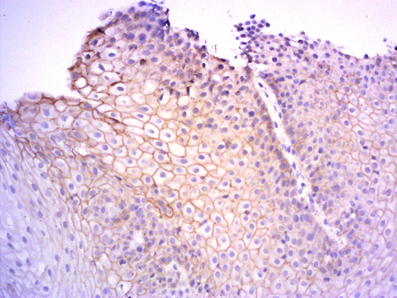

Patients were divided into 2 groups. The first group included 36 people (16 women – 44.4% and 20 men (55.6%)), the average age was 45.36±3.21years. Twelve patients were diagnosed with an erosive form, and 24 patients had a non-erosive GERD. The second group included 14 women (38.9%) and 22 men (61.1%), the average age of 42.94± 3.18years. Here, an erosive form was detected in 11, and non-erosive in 25 patients. As can be seen from Table 2, no significant differences in the manifestations of the disease were observed between the groups. The morphological study in the group of patients before treatment showed pronounced degenerative changes, erosion areas, parakeratosis, irregular regenerative changes, zones of papillomatosis and focal proliferation (Figure 1).

Figure 1 A fragment of the esophageal mucosa with severe degenerative changes, papillomatosis, focal proliferation of the epithelium. Hematoxylin and eosin staining, 50x magnification.